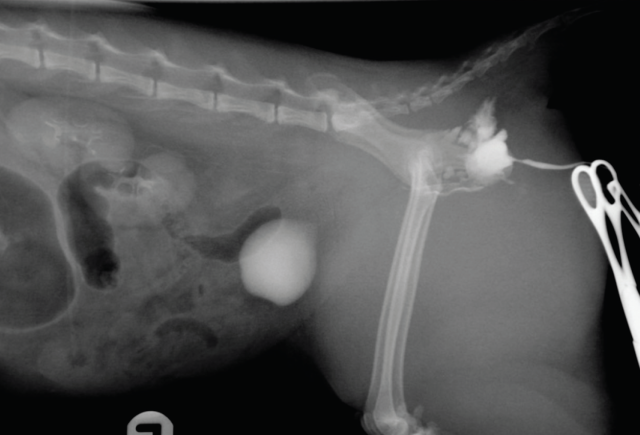

Urinary tract rupture can also occur with pelvic injury. A palpable bladder and the ability to urinate does not exclude urinary tract trauma (Aumann 1998). Baseline blood work indicating azotaemia and hyperkalaemia and a point-of-care ultrasound indicating abnormal abdominal fluid can help confirm a uroabdomen. Abdominocentesis and fluid analysis can provide further confirmation: in one case series the mean ratio of serum to peritoneal effusion for creatinine and potassium was 2:1 and 1.9:1 respectively (Aumann 1998). The perineal area should also be assessed for subcutaneous leakage from caudal urethral ruptures, but skin necrosis may take 24-48 hours to develop. A contrast study should be performed if there is confirmation of rupture or any uncertainty of patency (Figures 11 and 12). In the author’s institute, an intravenous urethrogram is generally performed prior to a retrograde urethrogram to confirm the ureters are patent.